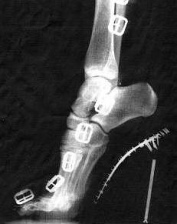

Ein Fuss in einem High-Heel-Stiefel mit Schnallen, Röntgenfoto der deformierten Fussstellung (die Schnallen erscheinen als "Fensterkette") [3].